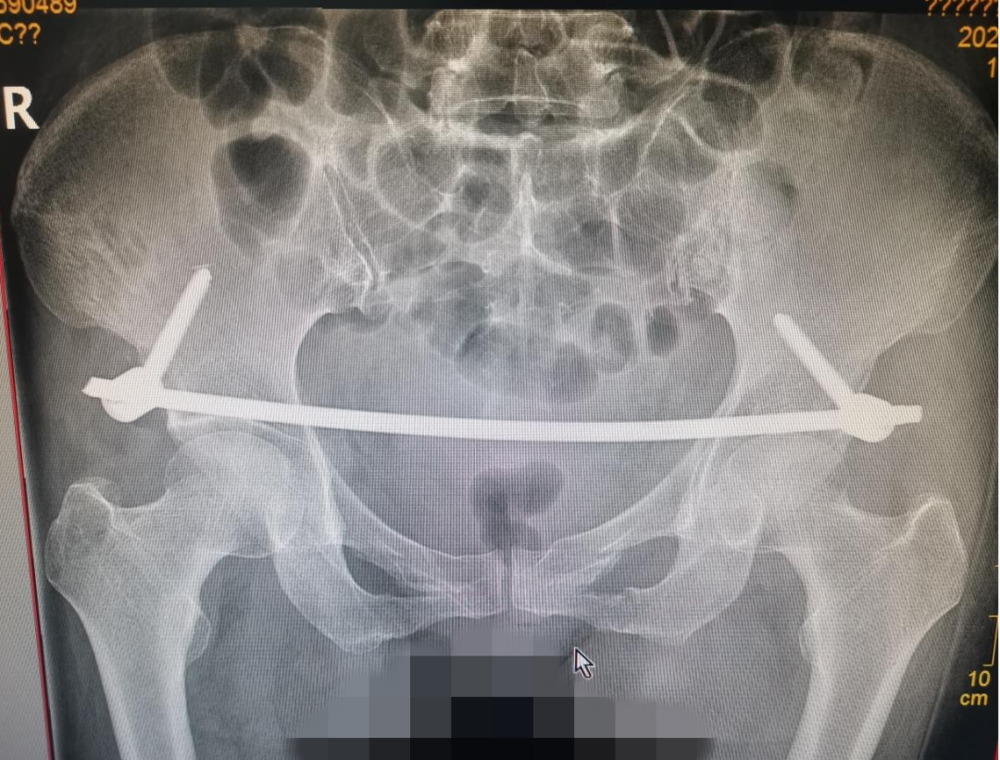

我院骨科團隊高度重(chóng)視葉某某的治療,經充分術前準備,由董明(míng)副(fù)主任、葉強醫師為患者在全(quán)麻(má)下行“經皮骨盆前(qián)環改良椎弓根釘-棒內固定術(shù)INFIX技術”,僅用不到(dào)1小時便成(chéng)功(gōng)完成了手術,僅2個3cm的手(shǒu)術切口,出血量約20ml,術(shù)後第二天患者就可以床上翻(fān)身及坐起,功能恢複良好。

近年來,應用外固定架原理,骨盆(pén)前環微創經(jīng)皮(pí)內固定(dìng)技術(INFIX技術)逐漸流行起來。INFIX技術固定結合了內固定和外固定的優點,揚長避短,針對此類患者,有效避免了術(shù)後深部感染,又避(bì)免了使用外固定的手術並發症(zhèng),讓患者在最佳治療時機獲得(dé)了骨盆(pén)環的穩定,並能早期開始功能鍛煉,最大程(chéng)度上降低了因傷致殘的機率。骨盆前環不穩定INFIX技術(shù)是(shì)真正意義上(shàng)的微創(chuàng)治療,該技術術後恢複快、對(duì)患者的日常生活影響小,有效減輕(qīng)了患(huàn)者的精神(shén)和經濟負擔,目前在國內僅有部分三甲(jiǎ)醫院已開展(zhǎn)此項技術。此項技術的開展,填補了縣域空白,標誌著武(wǔ)寧縣人民(mín)醫院外一科在骨盆(pén)骨折的微創治療技術上(shàng)又實現新的突破,將進一步規範和提升骨盆骨(gǔ)折救治能力,真(zhēn)正做到(dào)了大病不出縣,在家門口就能享受三甲醫院的治療水平,緩(huǎn)解了(le)群眾看病遠、看病難的(de)實際問題,為更好地保障縣域(yù)人民群眾身體健康打下了堅實的(de)基礎(chǔ)。